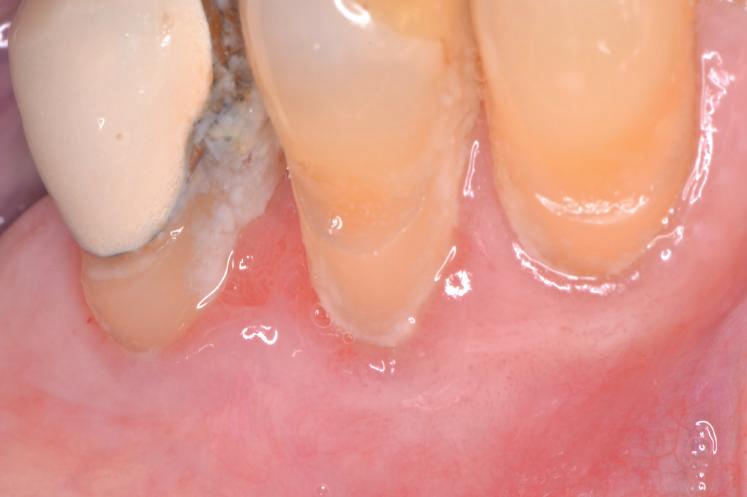

Datorită stabilității primare la inserare de aproximativ 35 Ncm pentru ambele implanturi, am optat pentru înșurubarea bonturilor intermediare conice Balance Base Narrow Straight GH 3.0 și vindecare transgingivală (fig. 2, 3). Inserarea acestor stâlpi s-a realizat la un cuplu de forțe de 25Ncm, cu ajutorul unei chei dinamometrice, aplicându-se ulterior cape de protecție (fig. 4). Vindecarea transgingivală postoperatorie a decurs fără complicații.

Figurile 1. Status clinic şi radiologic iniţial; 2. Bontul Balance Base Narrow Straight GH 3.0; 3. Bonturile Balance Base Narrow aplicate imediat post-inserare la 25 Ncm; 4. Aplicarea capelor de protecţie şi sutura; 5. Stâlpii de amprentă înşurubaţi la nivelul bonturilor Balance Base Narrow;

stâlpilor montați în etapa chirugicală (abutment/tissue level impression) (fig. 5). Amprenta finală s-a realizat cu ajutorul unei linguri individuale deschise în zona implanturilor 36 și 37, folosind vinylsiloxanether (Identium, Kettenbach) într-un singur